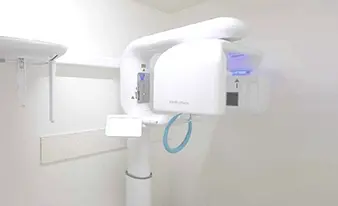

事前準備が重要

精密検査

に基づくインプラント手術

当院ではインプラント手術の前に精密検査を行い、

患者様が安心して手術に挑める環境に努めています。

- 歯科用CT